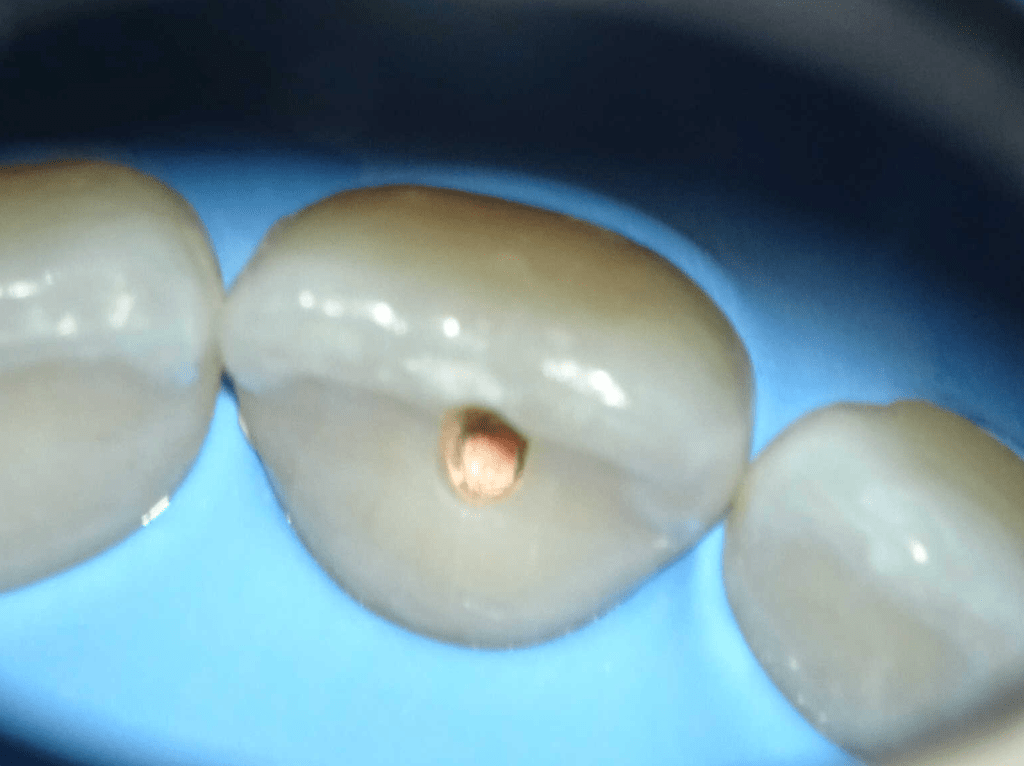

Acceso ultraconservador a través de incrustación reciente